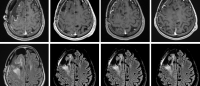

Glioblastoma samples before immunotherapy treatment from a patient who didn't respond to the therapy (left) and a patient who did (right). Images: Raul Rabadan / Columbia University.

To understand why only a few of these tumors respond to the immunotherapy drugs, Rabadan’s team took a comprehensive look at the tumor microenvironment—which includes the tumor itself and all of the cells that support it—in 66 glioblastoma patients before and after treatment with PD-1 inhibitors (nivolumab or pembrolizumab). Of these, 17 had a response to the drugs of six months or longer.